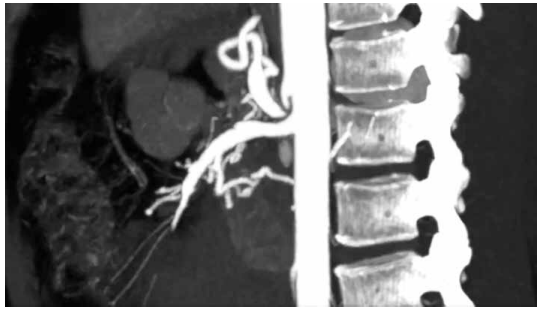

(Arquivo pessoal; imagem usada com autorização)

Analisando a imagem e a apresentação clínica, qual é o diagnóstico mais provável?